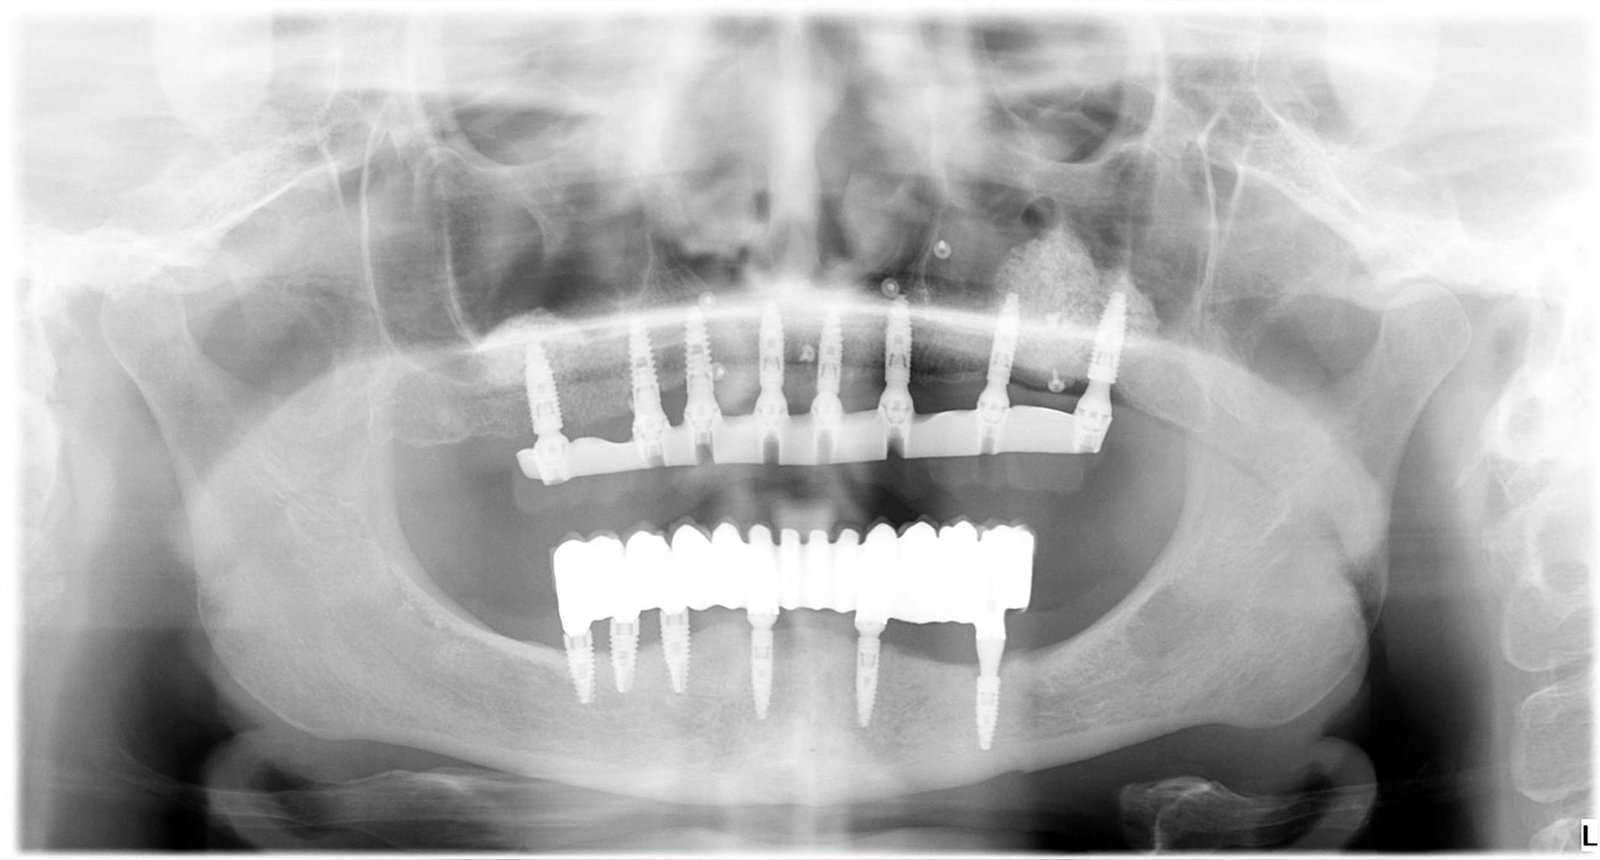

Caso 2 - caso de Carga inmediata

Buscaba una solución rápida y eficaz para volver a masticar y sonreír con normalidad. Mediante carga inmediata conseguimos rehabilitar su boca en una sola intervención, combinando rapidez, estética y funcionalidad.

Se confirma la correcta posición y fijación de los implantes, lo que permite colocar una prótesis fija inmediata con total fiabilidad.